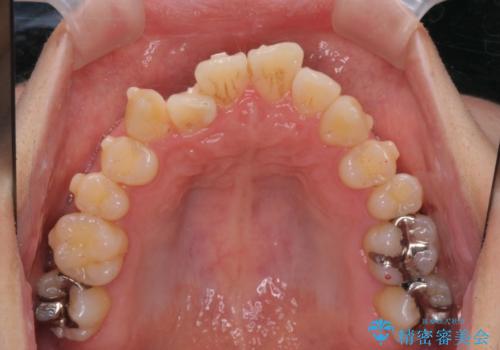

ねじれ・がたつきのある前歯を改善

- がたつき・すれ違い、ねじれのある前歯の見た目、噛み合わせの改善を希望され来院されました。

4本の小臼歯抜歯を避け、下顎前歯の1本抜歯の極力少ない抜歯本数で審美的な歯並びを得る治療計画としました。